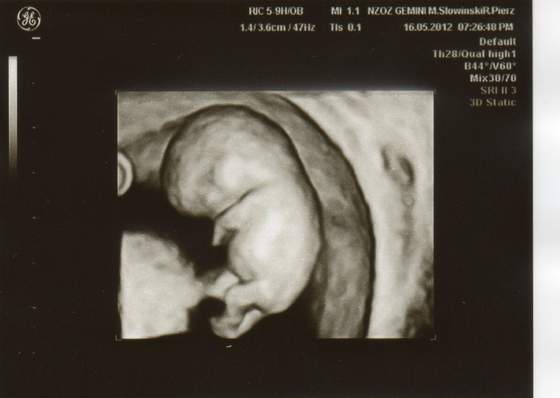

Po wczorajszej wizycie wstawiam obiecane zdjęcia mojego maleństwa :-) Morfologie mam idealną zato w moczu liczne bakterie Dostałam prenatal uro care i mam brać przez 10-12 dni i powtórzyć badanie moczu. Kolejna wizyta za 4 tyg :-)

Fiolka też mam podobne ale jak mi lekarz pokazał bijące serduszko to mu powiedziałam, że chcę ładne zdjęcie i mi na 3d przerzucił :-) zrobił zdjęcie z boczku, później powiedział "troszkę przodem, troszkę tyłem" i mam 3 śliczne fotki :-) A na koniec "no maluszku damy ci już spokój" - oj na fajnego lekarza trafiłam

A twój brząc wygląda pewnie identycznie tylko parę mm mniejszy :-)

Fiolka nie zeskanowałam z czystego lenistwa A drukarkę mam w innym pokoju i muszę lapa targać z kablami bo bateria kaput Jak coś to jutro zeskanuję ale moje nie jest takie ładne jak twoje bo nie widać tak rączek i nóżek - raczej taką rybkę